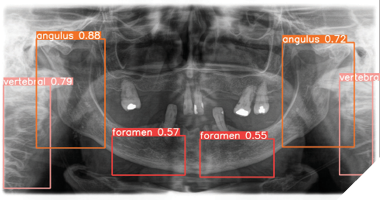

The Department of Oral and Maxillofacial Surgery at the Charité Berlin developed a deep learning model to detect CAC on PR (Fig. 3). Using a detection/segmentation model, researchers analyzed 6,404 PR from 5,621 patients, ranging in age from 18 to 99. They focused on 185 PR with confirmed CAC, matched with an equal number without, all meticulously annotated by three experienced clinicians. The dataset was enhanced with techniques like horizontal flipping, and images were normalized for consistency. The model was carefully tested in multiple rounds. It correctly identified about 90% of cases, missed very few, and achieved overall accuracy that shows it works reliably and is promising for real use. Dentists using it can confidently identify CAC during routine check-ups, acting as gatekeepers who refer patients to vascular specialists for further tests like Doppler ultrasound.

Fig. 3